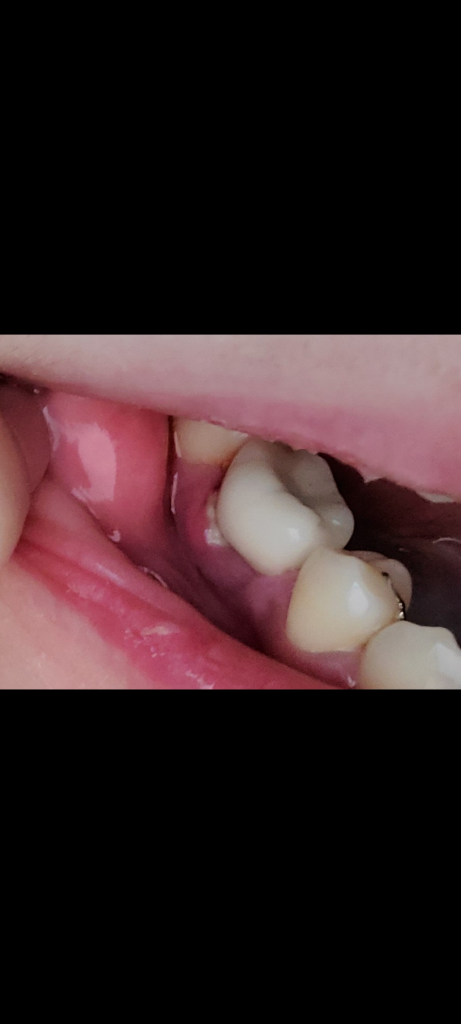

잇몸에 하얀 염증?같은게 생겼어요

임플란트 치아쪽 잇몸에 생긴지 4~5일 정도 된 것 같아요.

2주 전 스케일링 했고 그 이후 구강세정기를 매일 썼어요. 그리고 최근에 얼굴 마사지한다고 이쪽 볼을 좀 세게 문지르긴 했어요..

하얀게 처음보다 조금 커졌는데 치과를 가봐야할까요? 약국에서 약 사서 바르면 괜찮아질까요?

• 1번 째 사진